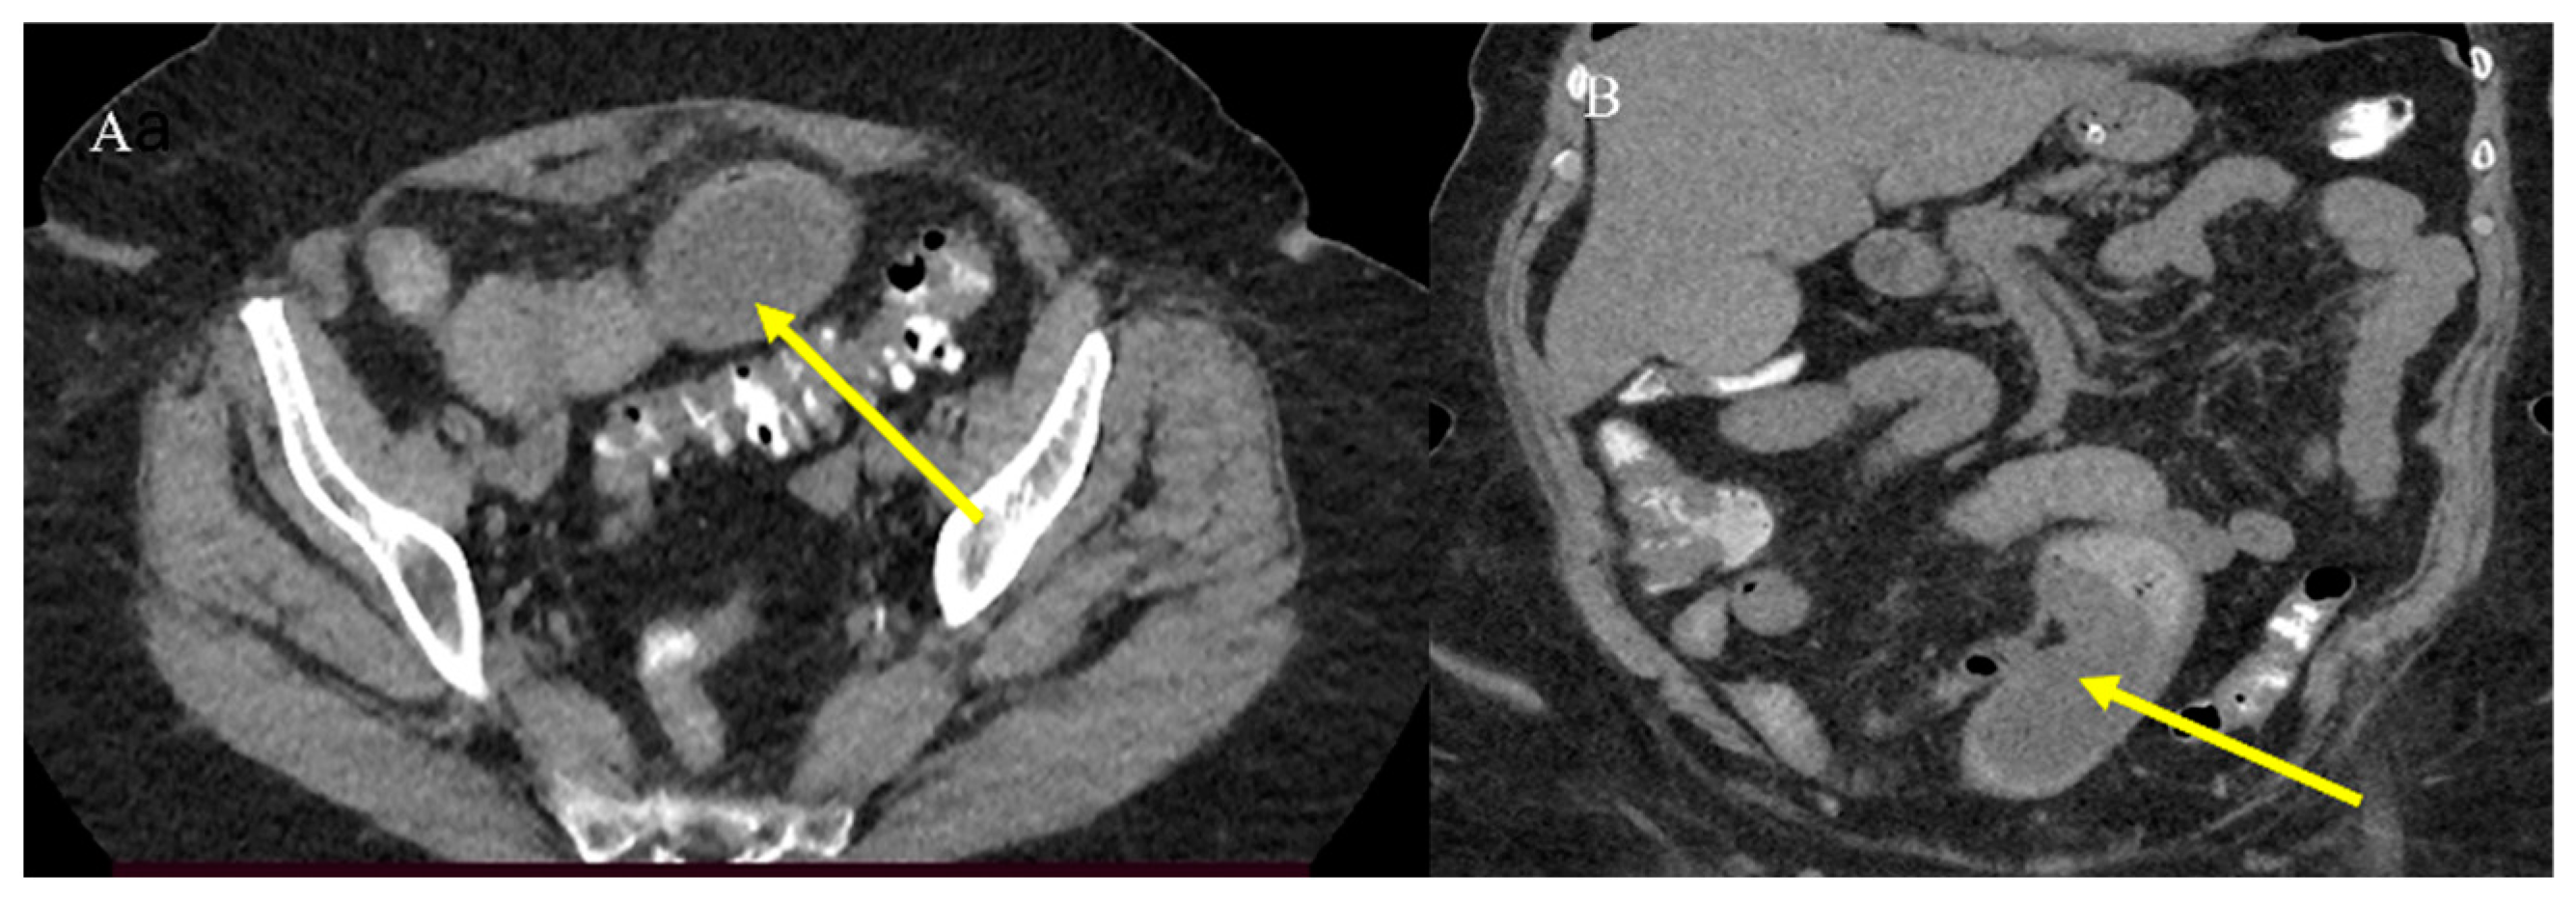

- Nelms, D.W.; Kann, B.R. Imaging modalities for evaluation of intestinal obstruction. Clin. Colon. Rectal Surg. 2021, 34, 205–218. [Google Scholar] [CrossRef]

- Paulson, E.K.; Thompson, W.M. Review of small-bowel obstruction: The diagnosis and when to worry. Radiology 2015, 275, 332–342. [Google Scholar] [CrossRef] [PubMed]